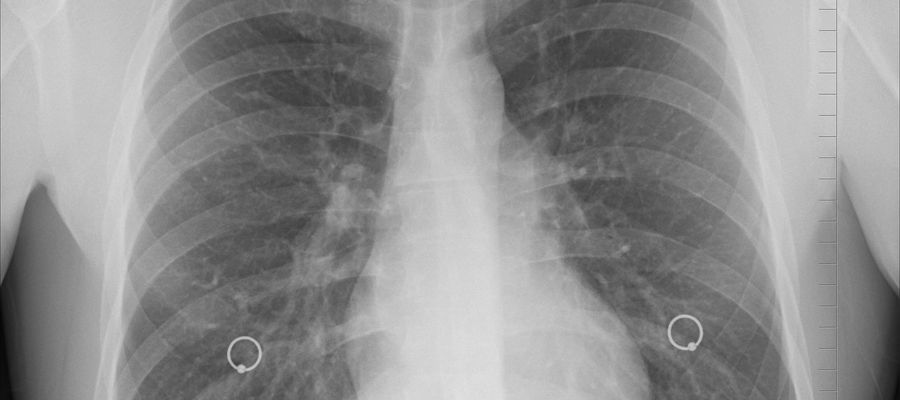

Mimo ogromnego postępu w medycynie rak płuca wciąż pozostaje jednym z największych wyzwań współczesnej onkologii. To złożona i niejednorodna choroba, która wymaga zarówno indywidualnego podejścia diagnostycznego, jak i personalizacji leczenia.